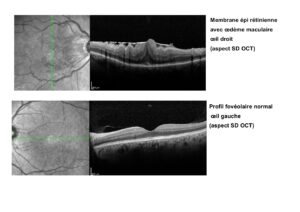

L’OCT (Optical Coherence Tomography), est l’examen clé de son diagnostic et de la recherche d’autres anomalies associées (décollement postérieur du vitré ou non, traction vitréo-maculaire, importance de l’œdème, soulèvement sous rétinien…).

Si les meilleurs gains d’acuité visuelle sont obtenus pour les visions initiales les plus basses, les meilleurs résultats finaux sont obtenus pour les acuités les moins altérées (pour revenir que rarement totalement à la normale). Il en est de même de l’aspect de la macula en OCT qui peut rester épaissie malgré un déplissement de sa surface.